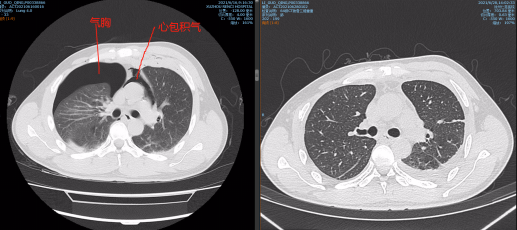

急诊医生对胸部伤口进行紧急加压包扎,随后经CT检查发现李师傅出现了心包积气与气胸,情况十分危险,随即联络胸外科王保毅主任进行紧急手术。

入院CT显示患有心包积气与气胸

术前术后心包积气情况对比